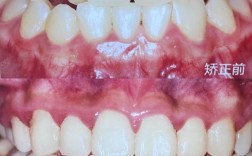

舌侧矫正将托槽和弓丝全部安装在牙齿舌侧面(内侧),从外部完全看不到矫正装置,被称为“隐形矫正的终极形态”,这一技术需通过数字化口扫获取牙齿数据,利用CAD/CAM设计个性化托槽(通常为金属材质,体积小于1.5mm²),再由医生精准粘贴于舌侧牙面。

舌侧矫正的美观性无可比拟,尤其适合演员、律师等对职业形象要求极高的群体,技术上,现代舌侧矫正采用“间接粘接技术”——在模型上预粘托槽后,通过转移板一次性粘贴到患者口内,将传统粘接时间从3-4小时缩短至1.5小时,且精度提升至10μm级,配合“轻力矫治”生物力学系统(如Ormco的STb托槽),可减少牙齿移动时的不适感,避免“大舌头”导致的发音障碍。